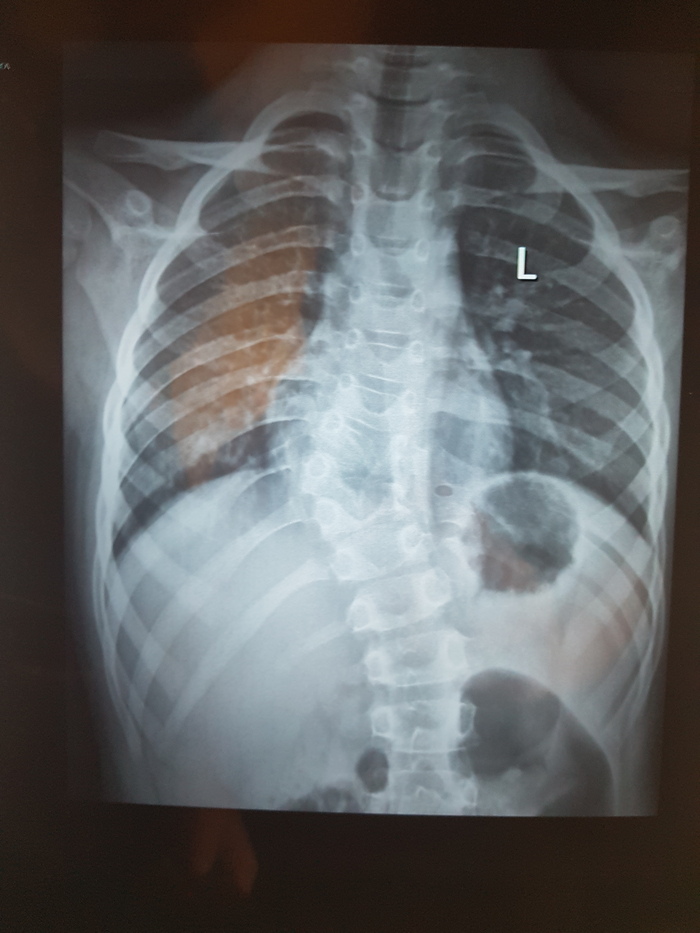

Нужна помощь вертебролога

Добрый день, сообщество! Нужна помощь, совет, консультация. Что угодно, что-бы мне понять что делать дальше. У ребенка при проведении рентгенографии в районой поликлинике выявили полупозвонок Th9.

В поликлинике хирург-ортопед настоятельно рекомендовал искать специалистов вертебрологов-ортопедов.  На пикабу встречаются совершенно разные специалисты, и может есть вертебрологи, ортопеды, которые смогут подсказать куда нам лучше обращаться. Насколько я понимаю, речь идет про операцию. Или возможны варианты? А если операция, то где ее могут сделать? И сколько примерно может стоить? И можно ли ее провести по ОМС или по квоте.

Вобщем, нуждаюсь в любой помощи, совете, консультации. Спасибо. Без рейтинга

Р.с. ребенку 7,5 лет. Территориально Москва